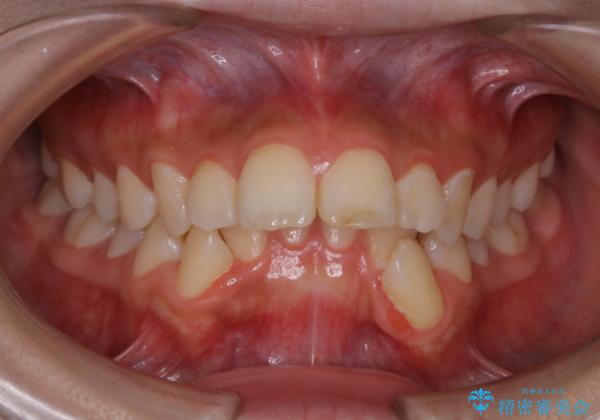

出っ歯と深い噛み合わせ:抜歯矯正で口元スッキリ!

- 出っ歯が気になるとご相談にいらした方です。抜歯して歯を並べました。深かった噛み合わせも改善させることが出来ました。

噛み合わせが元々深い方は一般的に噛む力が強く、治療に時間がかかる傾向にあります。治療前の想定よりも短期間でスムーズに治療を終える事ができ、大変喜んでいただけました。リテーナーによる保定もしっかり行っていただいており、後戻りなく快適にすごして頂けているとのことです。